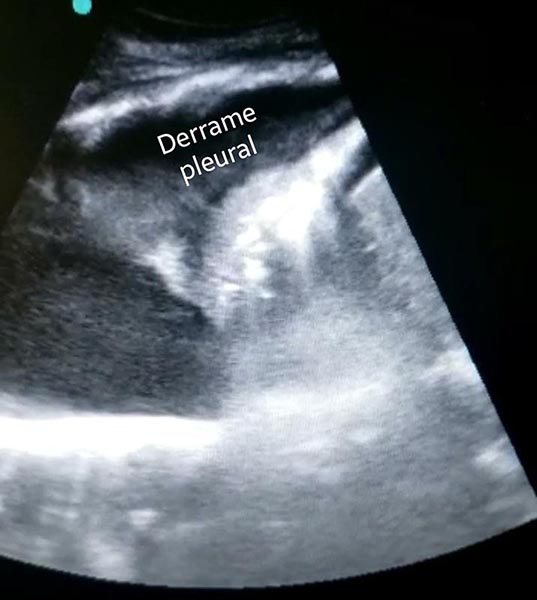

A imagem acima foi feita com um transdutor de baixa frequência, especificamente um probe convexo, na localização do espaço hepatorrenal, com o paciente na posição supina.

Podemos encontrar um conteúdo anecoico (preto) entre o parenquima hepático e a linha diafragmatica, provavelmente significando líquido ascitico.

Além disso, há derrame pleural, à esquerda do vídeo, também em preto, com achado adicional de consolidaçoes pulmonares em base direita.